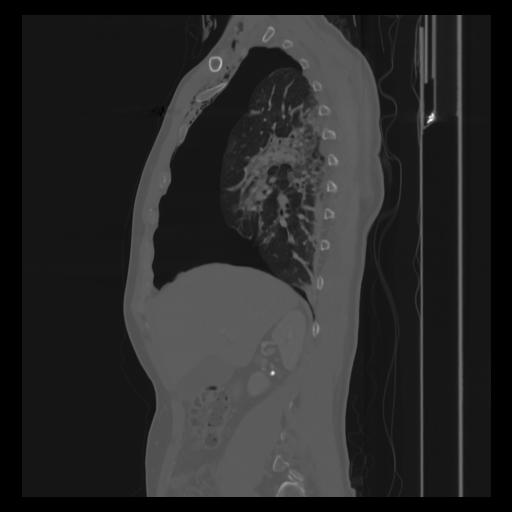

30 CUERPO,CE,Sagittal,3.000,CUERPO,Sagittal,